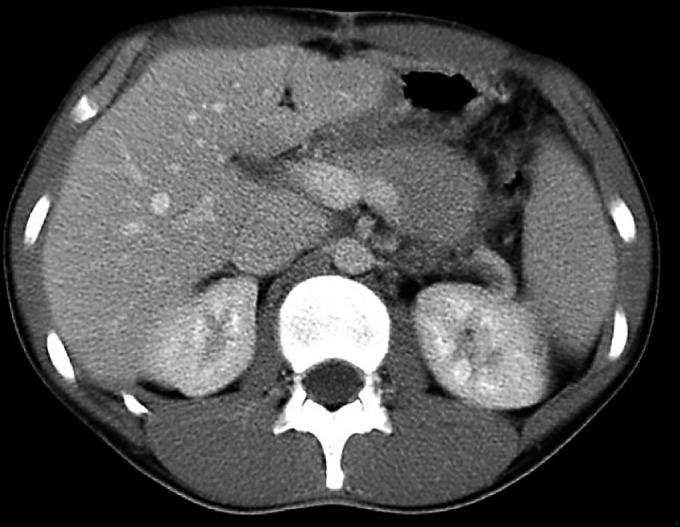

A 17-year-old rugby player was referred to our specialist unit after having been diagnosed with traumatic pancreatic transection, having presented 24 h after a sporting injury. Despite haemodynamic stability, at laparotomy he was found to have a diffuse mesenteric hematoma involving the large and small bowel mesentery, extending down to the sigmoid colon from the splenic flexure, and a large retroperitoneal hematoma arising from the pancreas. The pancreas was completely severed with the superior border of the distal segment remaining attached to the splenic vein that was intact. A distal pancreatectomy with spleen preservation and evacuation of the retroperitoneal hematoma was performed.

一名17岁的橄榄球运动员在运动损伤24小时后被诊断为创伤性胰腺横断,随后被转诊至我们的专科病房。尽管血流动力学稳定,但在剖腹手术中发现他有弥漫性肠系膜血肿,累及大小肠系膜,从脾曲向下延伸至乙状结肠,还有一个源于胰腺的巨大腹膜后血肿。胰腺完全横断,远端部分的上缘仍与完整的脾静脉相连。进行了保留脾脏的远端胰腺切除术并清除了腹膜后血肿。